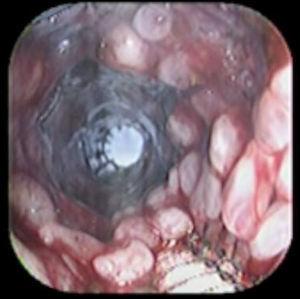

Case reportA 41-year-old man underwent elective laparoscopic Heller myotomy for achalasia; during the procedure a perforation of the esophageal wall was observed, and primary closure of the defect was attempted. The patient started with PO on day three, but he complained of chest pain and fever. Immediately CT scan with oral contrast was performed. A free leakage at esophago-gastric junction was observed. A 15 cm PSEMS (Ultraflex esophageal NG covered (120 mm) stent, Boston Scientific, Natick, MA) was placed across the defect, leading to the distal 1.5 cm non cover into the stomach and the proximal 1.5 cm non cover at 30 cm from incisor (Figure 1). A control CT scan with oral contrast showed good position of the stent, without evidence of leakage. The patient's clinical status improved and began to swallow normally, but showed numerous episodes of reflux despite PPI use. We leave the PSEMS for 26 days beside the reflux symptoms. During the endoscopic procedure to remove the stent the presence of tissue embedding along the covered portion of the PSEMS was noted (Figure 2). The stent was pulled out with an alligator forceps with out major complications and the cover of the PSEMS was seen to be totally destroyed (Figure 3).

Figure 3. After removal of the stent, the image shows total destruction of the covered portion.